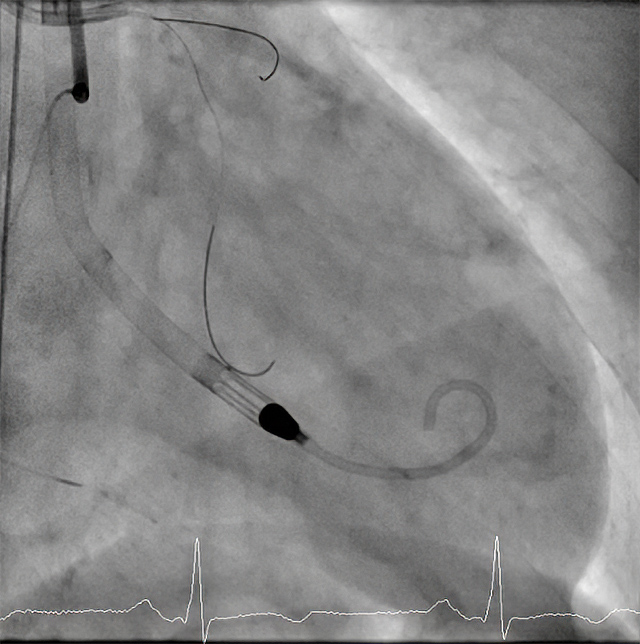

60歲傅先生(化名),日前因胸部悶痛來到高醫岡山醫院住院,經心導管診斷為左主幹冠狀動脈嚴重狹窄,合併三條冠狀動脈血管同樣嚴重病變並合併慢性全阻塞,心臟超音波顯示嚴重心臟衰竭,左心室收縮功能異常,經會診心臟血管外科醫師進行評估,由於繞道手術風險高,在心臟內外科醫師與病人家屬共同討論後,決定施行經皮冠狀動脈介入手術治療。惟考量心臟衰竭,左主幹合併多條冠狀動脈嚴重狹窄,介入手術風險極高,高醫岡山心臟血管內科郭炫孚主任帶領團隊在術前裝置「微型心室輔助器(Impella)」,避免於困難手術中、甚至術中心臟停止時仍可以維持患者的心臟功能與血壓。傅先生在醫療團隊合作之下,順利完成手術,打通血管與慢性全阻塞,於手術當天即移除Impella。傅先生在手術之後經過休養,心臟功能恢復良好。

Impella是一種小型的心室輔助裝置,通常通過股動脈插入並進入左心室,能夠將血液從左心室泵送到升主動脈,維持血液循環。其工作原理是提供一個臨時的血液循環輔助,於重度心臟衰竭或心臟疾病的患者,因心臟功能低下而無法有效地維持正常的血液循環下,可以減輕心臟的負擔,讓醫生能夠安全地進行心導管手術。

Impella支持下進行高危心導管手術